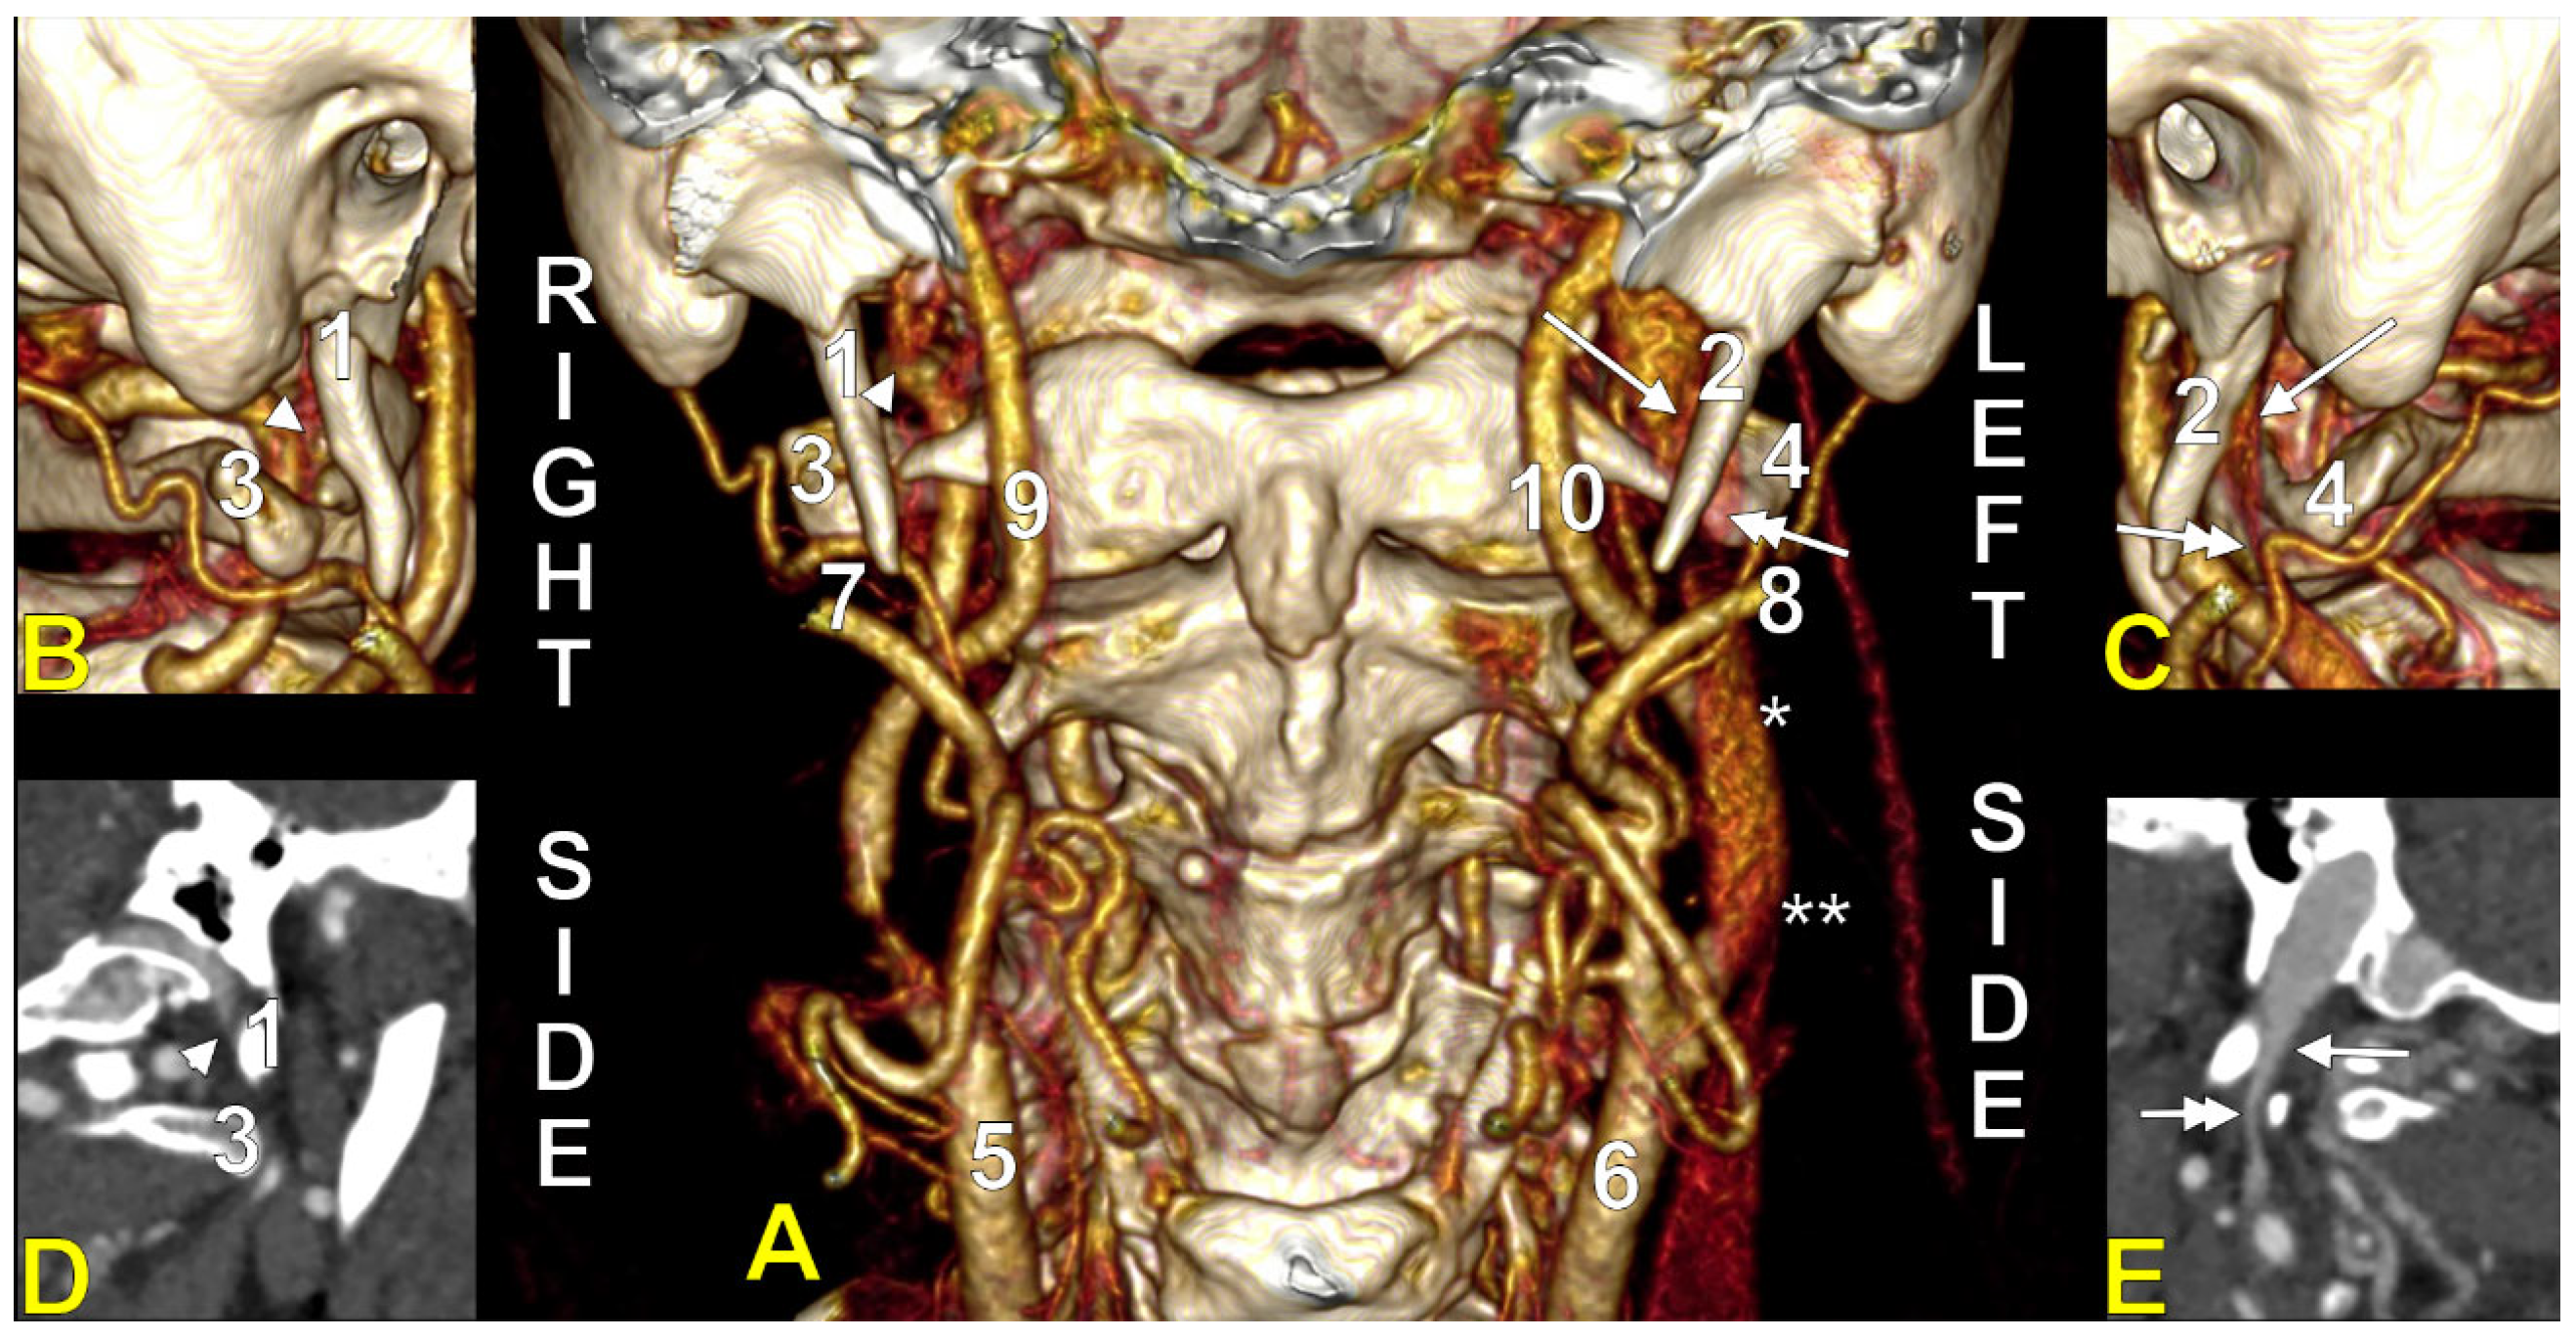

Cases have shown that a tortuous ICA can externally compress the IJV, resulting in IJV stenosis. Symptoms are often nonspecific and may be misattributed to other conditions, resulting in a delayed diagnosis. Although two cases of bilateral IJV stenosis by tortuous ICAs were reported previously [166], this condition seems to be overlooked. While the specific literature on atheromatous carotid artery compression of the IJV, shown in Figure 7, Figure 8 and Figure 9, appears limited, the concept is anatomically and pathophysiologically plausible because of the following: (a) anatomical proximity—the CCA, ICA, and IJV run nearby within the carotid sheath; (b) mass effect—atheromatous plaques can cause arterial wall thickening and luminal irregularity; and (c) vascular remodelling—atherosclerotic changes can alter vessel geometry. A dynamic pseudo-nutcracker jugular compression may be considered when the IJV is pinched between the SCM and the CCA (Figure 9). Other studies did not search for specific muscle details related to IJV compression [40,133,174], although these may add, at different cervical levels, to a nutcracker compression between the atlas and the SP (Figure 9 and Figure 10).

A right dominant IJV is presented in Figure 11. One may observe that the IJV course, as related to the carotid axis, is bilaterally asymmetrical; the left IJV is lateral to the carotid axis, while the right IJV is posterolateral to the carotid axis. Seemingly, the bilateral symmetry of the IJV/carotid topography was consistently overlooked in previous studies [199]. An ultrasonographic study on 80 critically ill patients found that in 62.5% of cases, asymmetric IJVs [44]. The right IJV was dominant in 68% of cases, and the left IJV in 32% [44]. The IJVs were studied using transverse sections, 15 mm above the cricoid cartilage [44].